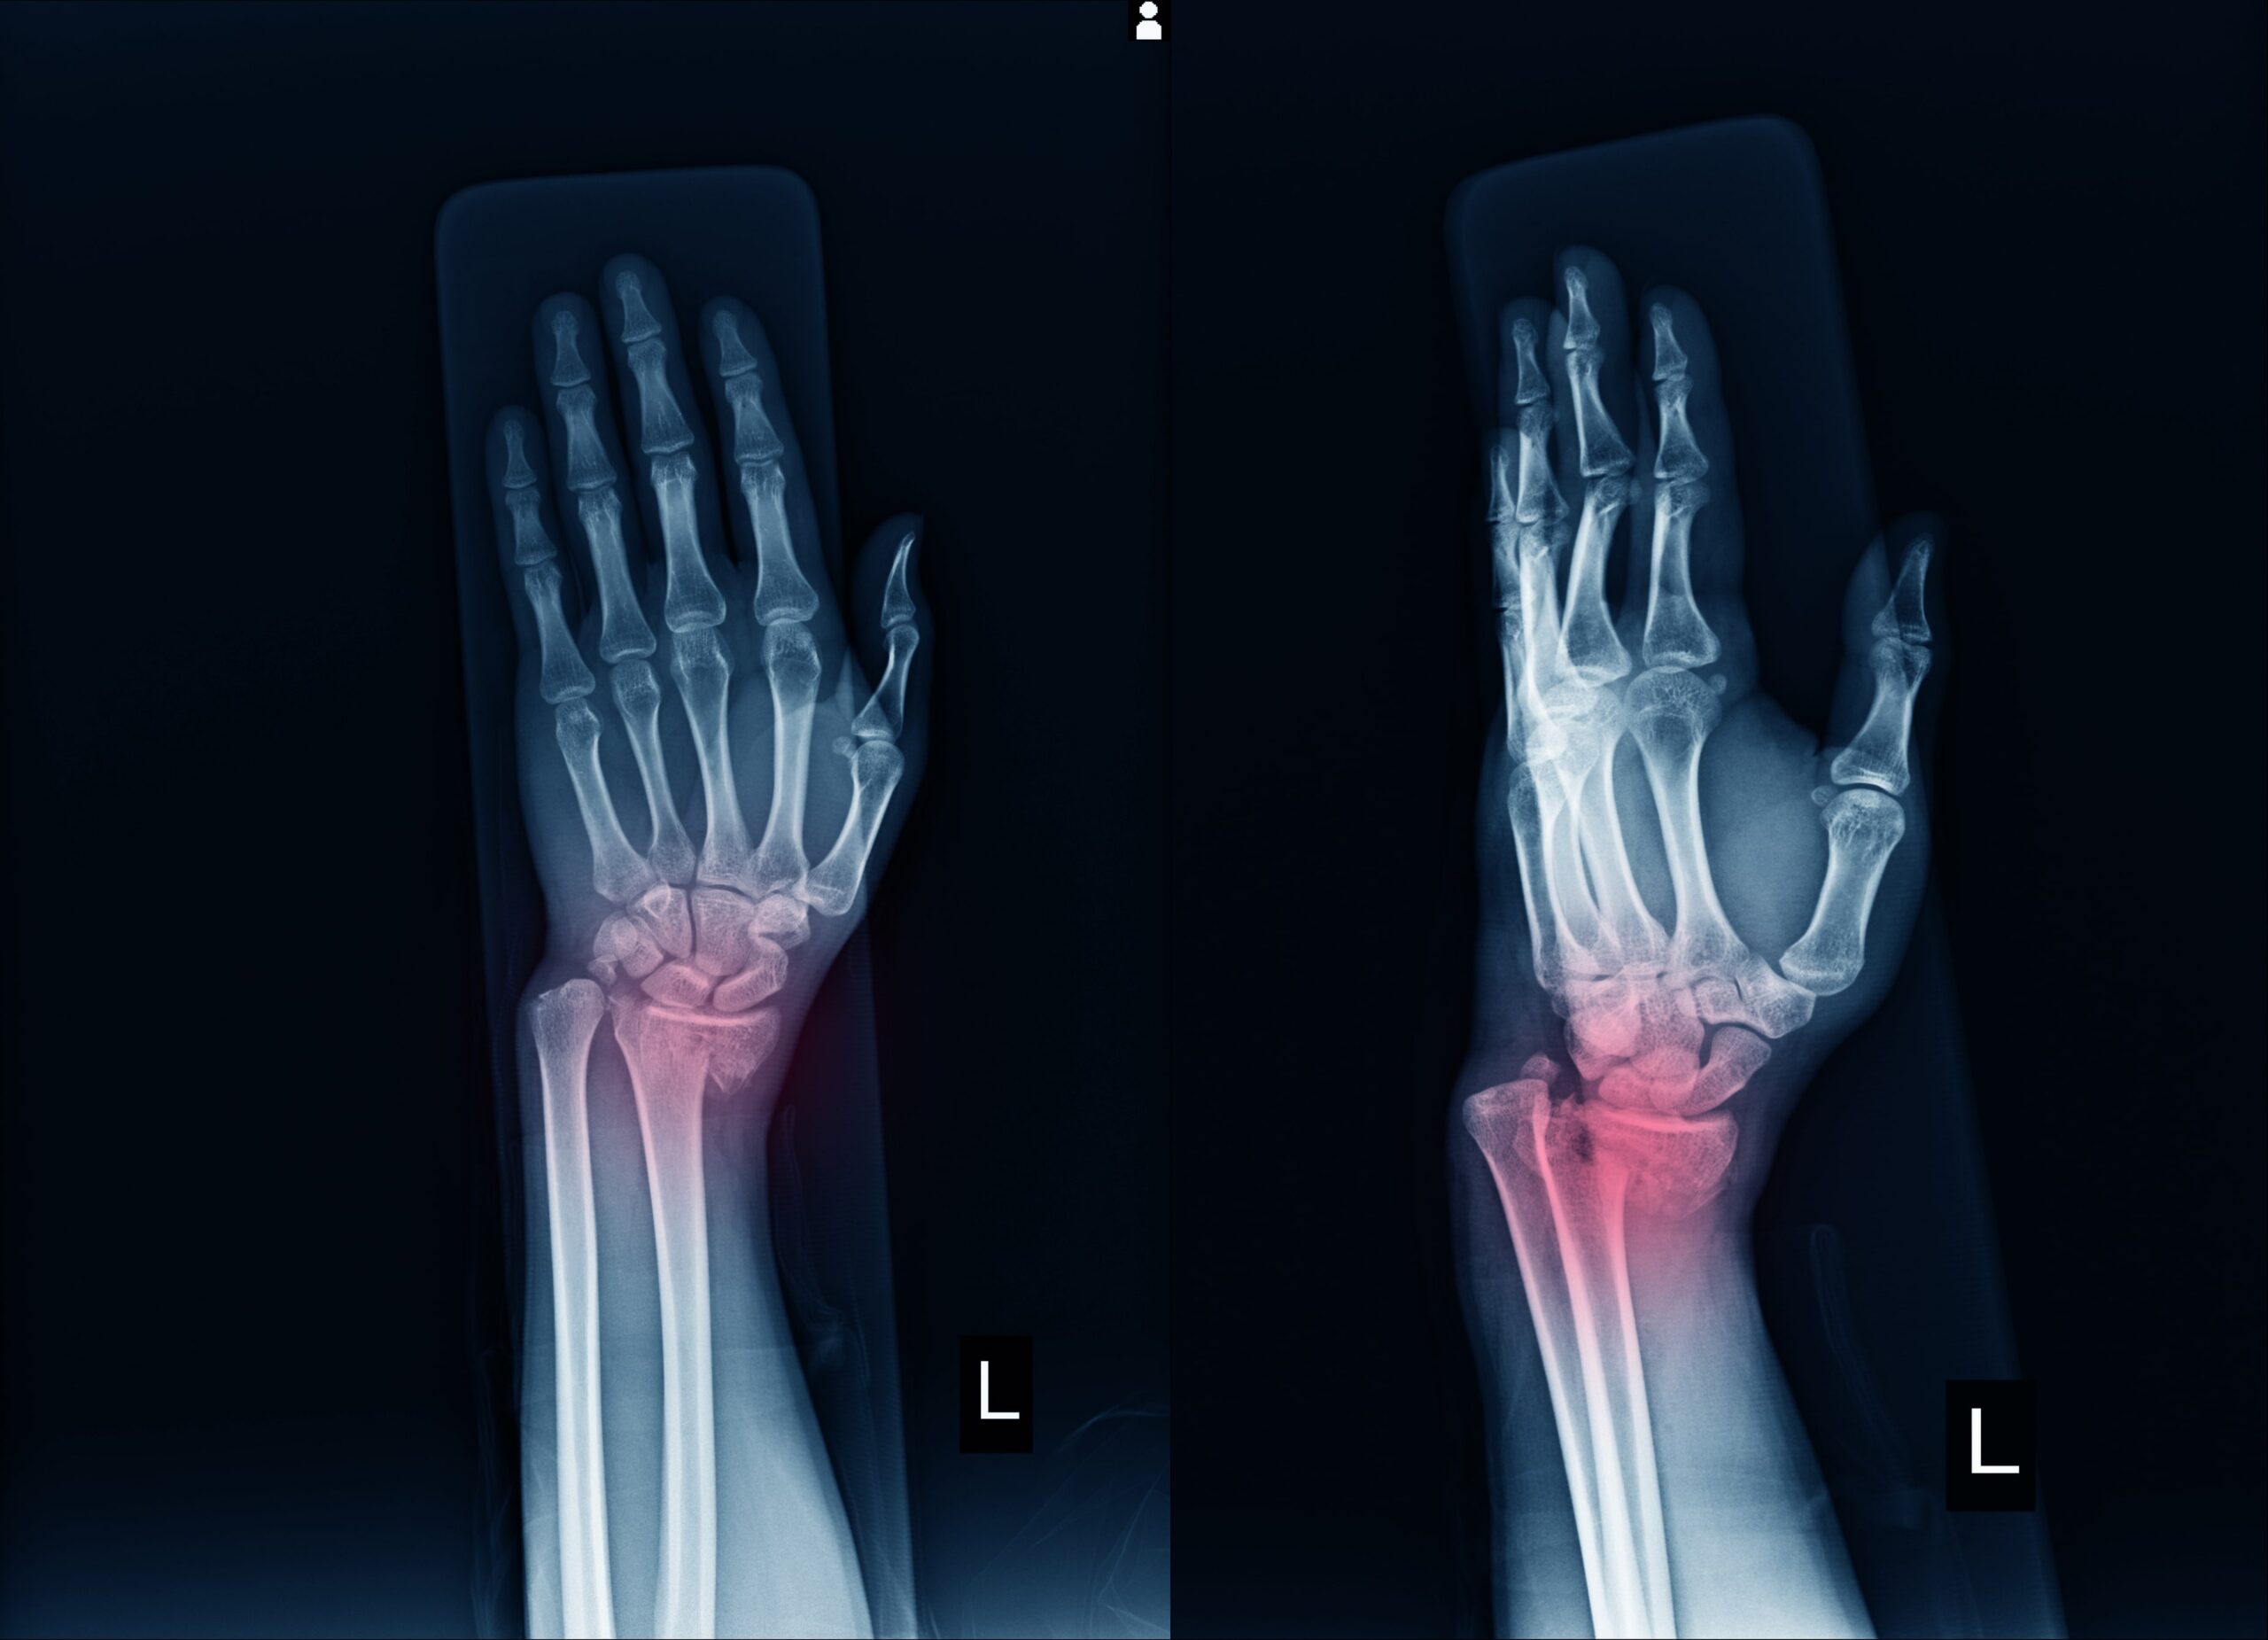

Eine distale Radiusfraktur ist ein Knochenbruch im Bereich des Handgelenks. Dies kann nicht nur schmerzhaft, sondern auch belastend für Ihre Mobilität und Lebensqualität sein. Ob durch einen Sturz, Sportverletzungen oder andere Unfälle – eine schnelle und präzise Behandlung ist entscheidend für eine vollständige Heilung.

Die distale Radiusfraktur (Bruch der Speiche nahe dem Handgelenk) ist die häufigste Fraktur beim Menschen, insbesondere bei älteren Menschen und Kindern. Sie entsteht fast immer durch ein Trauma, meist bei einem Sturz auf die ausgestreckte Hand.

Typische Frakturtypen:

- Colles-Fraktur (häufigste Form): dorsale Dislokation der distalen Speiche

- Smith-Fraktur: palmare Dislokation (seltener, meist bei Beugesturz)

- Trümmerfraktur: bei starker Krafteinwirkung

- Intraartikuläre Fraktur: Gelenk ist mit betroffen → meist instabil

Es erfolgt eine klinische Untersuchung, sowie ein Röntgen, um die Diagnose zu sichern und den Eingriff zu planen. In gewissen Fällen ist ein CT (oder MRT) notwendig, um die Frakturanteile genau beurteilen zu können.